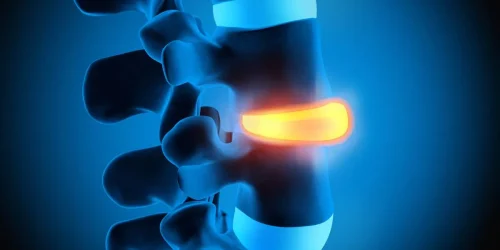

There are 30 different causes of chronic back pain. The most common is an injury to the spinal disc. Spinal disc injuries are caused by a tear in the back wall of the disc, where some of the nuclear material herniates into the tear and causes inflammation. Inflammation is your body trying to repair that tear — it’s constantly attacking the jelly trying to get rid of it. That’s what causes chronic back pain most commonly.

What I’m getting at here, folks, is that the scoliosis is just a red herring. In other words, it’s a finding on exam — with MRI, X-ray, or CAT scan. You see the scoliosis and the surgeons think we’ve got to fix the scoliosis to fix the patient’s back pain. But that is not true.